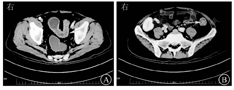

体温为36.3 ℃,脉率为84次/min,呼吸频率为16次/min,血压为124/76 mmHg(1 mmHg=0.133 kPa);神志清楚,全身浅表淋巴结无肿大,双肺呼吸音清,未闻及干湿性啰音,心率为84次/min,心脏瓣膜听诊区未闻及病理性杂音;腹部平坦,右侧腹部可见一长约10 cm陈旧性手术瘢痕,全腹无压痛和反跳痛,无肌紧张,肠鸣音未见异常。入院后血常规检查示白细胞计数为14.46×109/L,中性粒细胞计数为13.17×109/L,中性粒细胞占比为0.91;超敏C反应蛋白为14.1 mg/L,ESR为27 mm/1 h,白蛋白为35.3 g/L;粪便隐血试验和粪便白细胞均阳性;肠道菌群分布Ⅲ度失调;肝肾功能、甲状腺功能、自身抗体系列(抗核抗体、抗Sm抗体、抗双链DNA抗体、抗SSA抗体、抗Scl-70抗体、抗Jo-1抗体等)均未见明显异常;T-SPOT、CMV、EB病毒、艰难梭菌和粪便细菌培养均为阴性。2020年9月22日,患者复查肠镜(图3)示降结肠狭窄,黏膜粗糙,多发糜烂、溃疡,降结肠黏膜可见多发增生性指状突起,黏膜脆性增加,血管纹理紊乱,直肠病变较轻,内镜诊断为结肠溃疡,溃疡性质需结合病理检查结果判定。病理检查(图4)示慢性活动性肠炎,形态提示UC。2020年9月26日肠道双源计算机断层扫描(computed tomography,CT)(图5)检查示乙状结肠、降结肠、横结肠肠壁肿胀、增厚,黏膜强化,考虑为炎性改变、双肾萎缩、右侧髂窝移植肾。

影像科赵宏亮主治医师:患者入院肠道双源CT检查示本体双肾体积明显缩小,肾皮质萎缩且强化减低,右侧髂窝内移植肾皮质强化良好,肾动脉显影良好,肾盂、肾盏未见扩张、积水;患者肠道病变主要位于降结肠、乙状结肠,呈现弥漫性的肠壁略增厚,降乙交界处为主,肠腔内见结节样软组织影,导致肠腔狭窄,呈不完全性梗阻,无IBD典型影像学表现。肠系膜动脉和分支、肠系膜静脉和属支均未见血栓。患者有腹泻、便血症状,肠镜检查示结肠多发溃疡,肠道双源CT检查可排除缺血性肠道改变,仍需结合临床表现、肠镜、病理检查结果综合判断。